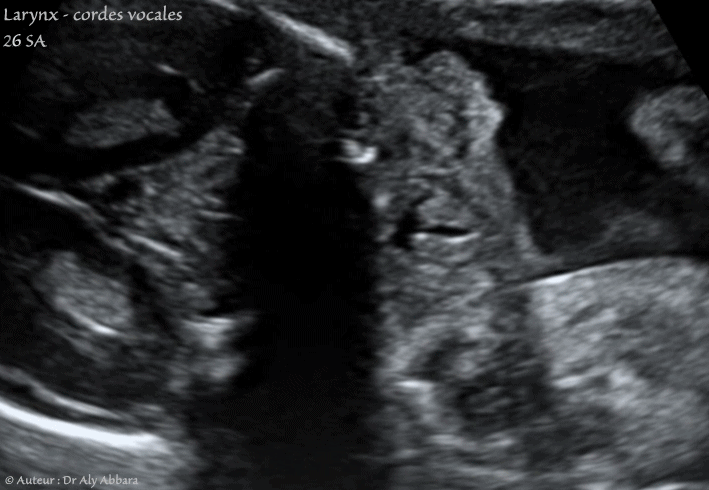

Images échographiques animées montrant, la motricité des cordes vocales du larynx fœtal au cours des mouvements respiratoires in-utero.

Fœtus âgé de 26 SA.